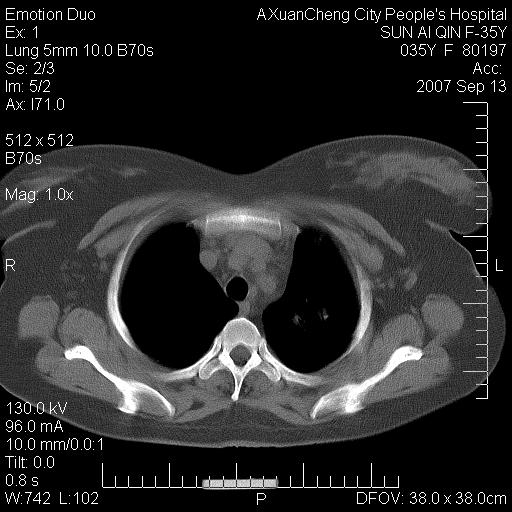

以下是引用天南地北在2007-9-13 13:43:00的发言:[br]考虑双肺、肺门侵润

以下是引用ydx_74在2007-9-13 15:42:00的发言:[br]仅看片,考虑右上肺癌并双肺转移,结合病史,考虑肺门、肺内淋巴侵润

以下是引用同在2007-9-13 15:08:00的发言:[br]支持肺门及双肺侵润.